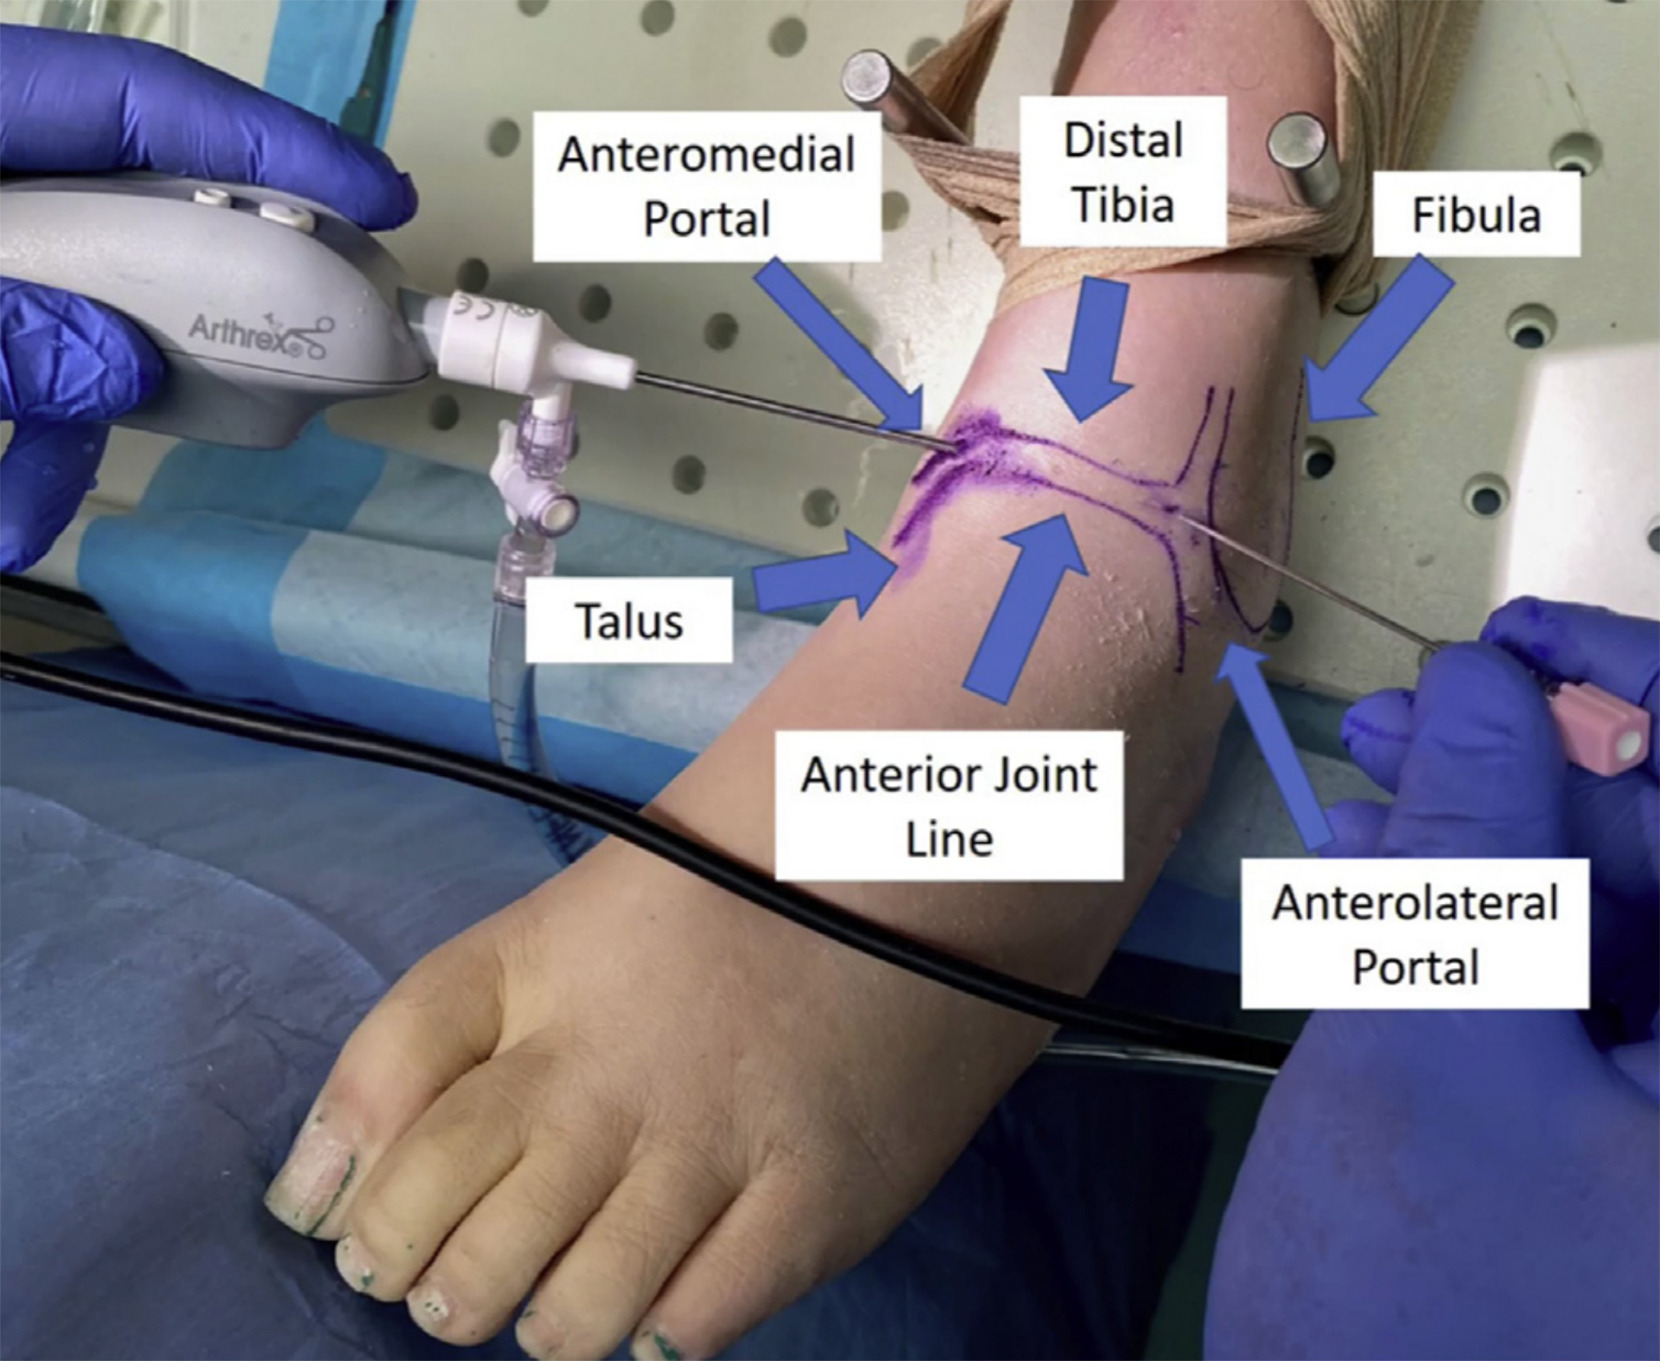

Ankle Arthroscopy

What Is Arthroscopy?

Arthroscopy is a minimally invasive surgical procedure used to diagnose and treat joint problems. During the procedure, a small camera called an arthroscope is inserted into the joint through tiny incisions. This allows the surgeon to view the internal structures on a screen and perform precise repairs using specialized instruments.